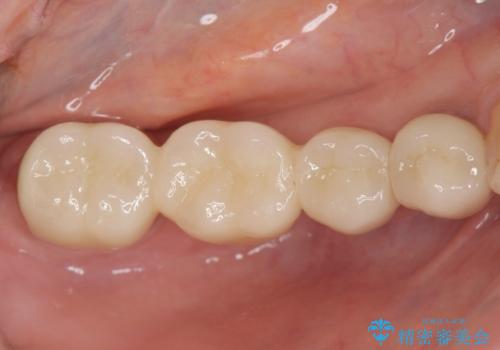

臼歯部メタルフリー再補綴

- 治療してからの年月が経過し、かみにくくなったブリッジ・クラウンを全てやりかえたいと希望され来院されました。

クラウン・ブリッジを作り替えるにあたり虫歯の徹底的な除去・根管治療のやり直しを行い今後やり直しをしなくて済むような環境を整えていきます。

装着して長期間経過したブリッジやクラウンは隙間から細菌が侵入し虫歯が再発してしまっていることがあります。

長期的に問題のないブリッジ・クラウンを作製するため、虫歯をしっかりと除去すること精密な根管治療を行うことが肝要です。